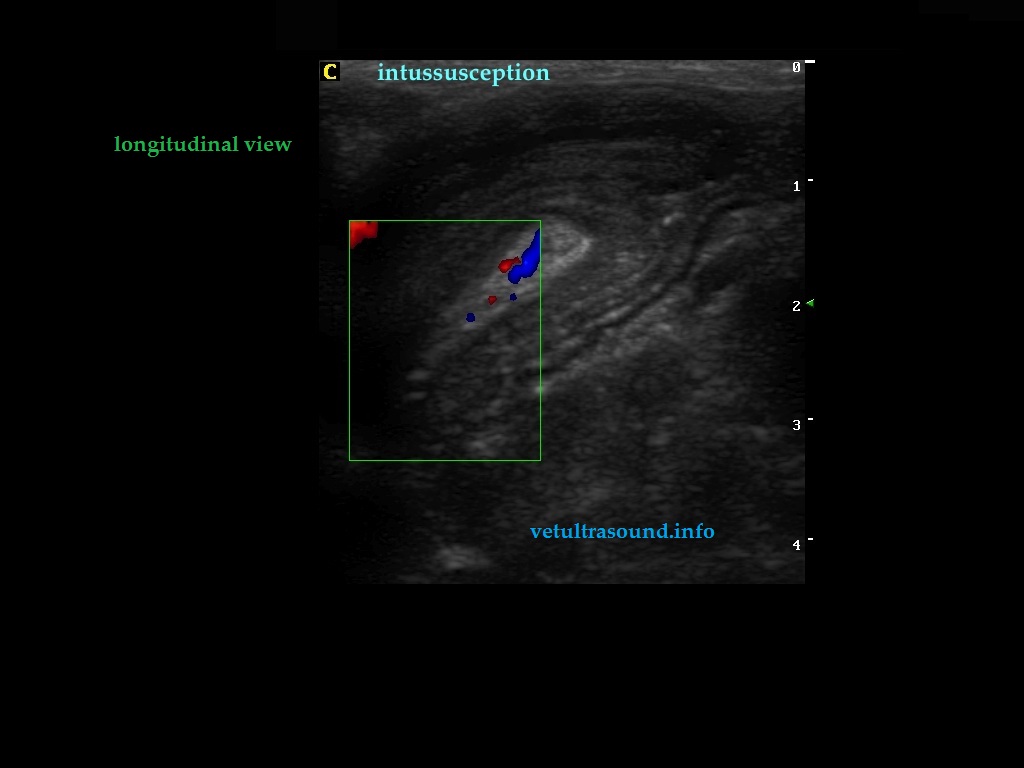

Findings: Distention of large part of the small intestine, caused by intussusception. The blood flow in the mesenteric arteries which supplied the intussusception was normal. The mesenteric lymphnodes were enlarged. A small amount of ascistic fluid was noted.

Ευρήματα: Στον υπερηχοτομογραφικό έλεγχο της κοιλίας βρέθηκε παρουσία εγκολεασμού σε τμήμα του λεπτού εντέρου. Η αιμάτωση των μεσεντέριων αγγείων του εγκολεσθέντος τμήματος εκτιμήθηκε φυσιολογική. Οι μεσεντέριοι λεμφαδένες βρέθηκαν διογκωμένοι με αντιδραστική ηχομορφολογία. Υπήρχε μικρή ποσότητα ασκιτικού υγρού. Οι υπόλοιπες εντερικές έλικες που αφορούσαν το τμήμα του λεπτού εντέρου πριν τον εγκολεασμό βρέθηκαν διατεταμένες .